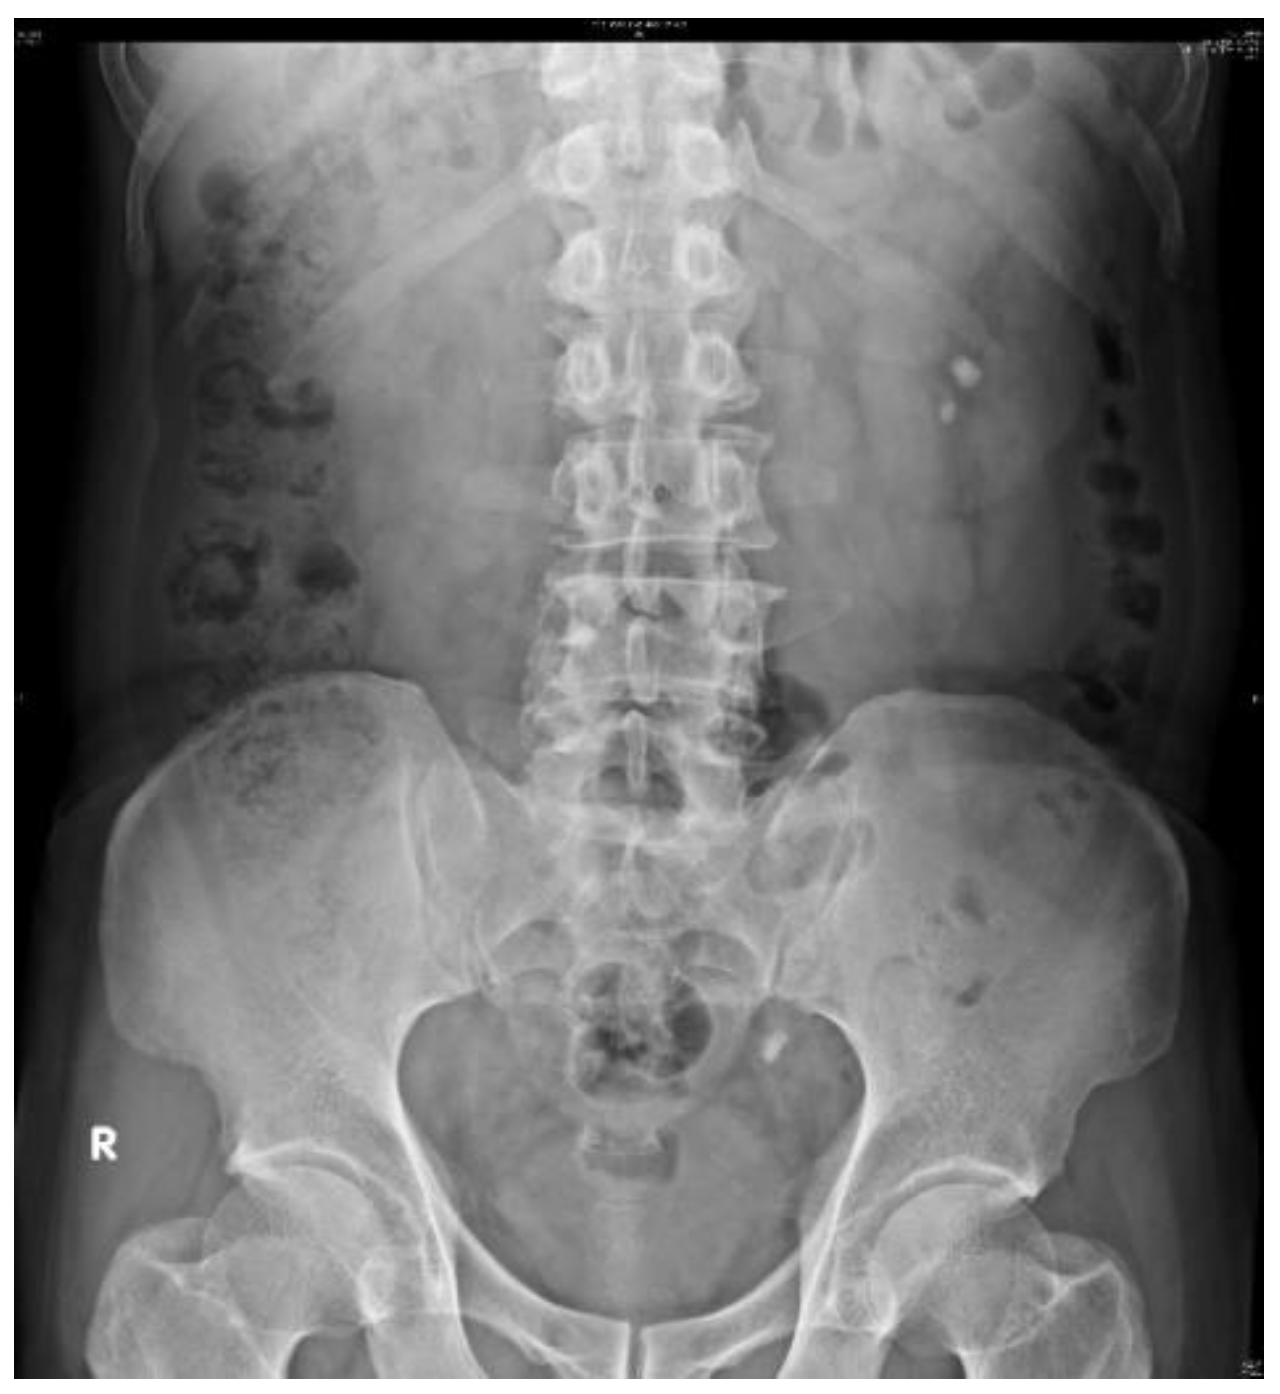

2.2. Datasets

2.3. Image Preprocessing